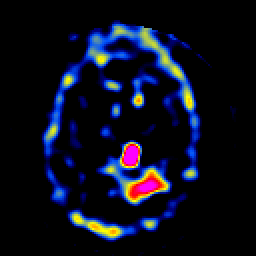

SPECT TL Study #8 -- Slice #38

[Home][Help][Clinical][Tour 1][Tour 2][Tour 3] Slice 38